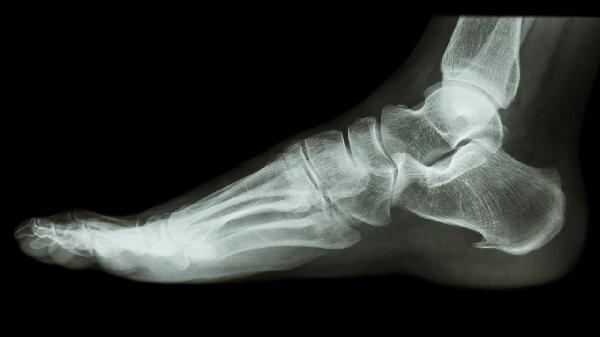

脚跟骨折多久能走路 注意脚跟骨折走路不宜过早

脚跟骨折后一般需要8-12周才能逐步恢复行走,实际恢复时间受到骨折类型、固定方式、康复训练、年龄和并发症等因素影响。过早负重行走可能导致骨痂移位或延迟愈合。